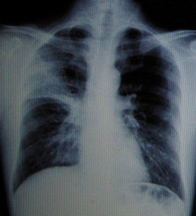

男性,40歲。發(fā)熱4天,伴黃痰。

A.右上肺不張

B.右上肺炎

C.右上肺癌

D.右上胸膜肥厚

『正確答案』B